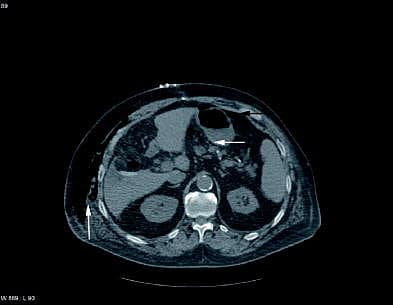

To dage efter operationen blev der bemærket luft i sugedrænet, hvilket tolkedes som falsk luft fra en drænsamling. Luftmængden tiltog, og på tredjedagen postoperativt blev der foretaget akut computertomografi (CT) af abdomen. CT'en viste store mængder fri luft intraabdominalt, en smule luft i lille sæk og subkutant emfysem. Patienten fik foretaget eksplorativ laparotomi, og man fandt et perforeret ulcus på bagsiden af ventriklen højt på curvatura minor.

Billedet viser en CT af abdomen. Vandret hvid pil: luft i lille sæk, vandret sort pil: fri intraabdominal luft, lodret hvid pil: subkutant emfysem.